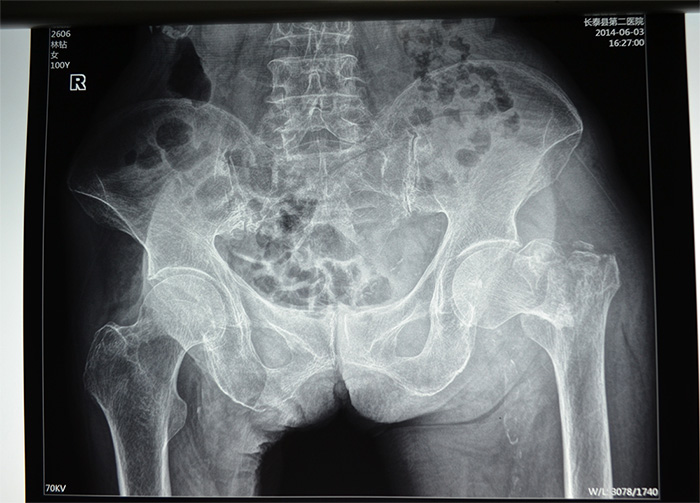

据家属介绍,百岁老人身体还不错,平时生活能自理,还能做家务。5月20日上午,她在洗衣服的时候,由于地面湿滑,摔倒在地,当时左腿就无法站立,送到当地伦理片

拍片,发现左腿髋部骨折严重,且错位明显。考虑患者高龄,骨折严重,手术风险高,技术难度大,当地伦理片

林老太入三院时,左腿的髋部骨折处已翻转90度,还出现短缩移位,左腿比右腿短了5—6公分。由于疼痛,每次大小便,对老人来说都是一次折磨,她也不敢正常摄入食物,导致出现低蛋白,且原先就有高血压的症状,心血管功能比较差,手术风险极高,如果采用传统的骨折开放复位钢板固定术,对于高龄特别是骨质疏松患者,手术失败率很高,同时卧床时间长达三四个月,极易引发并发症。骨科主任刘忠国说。